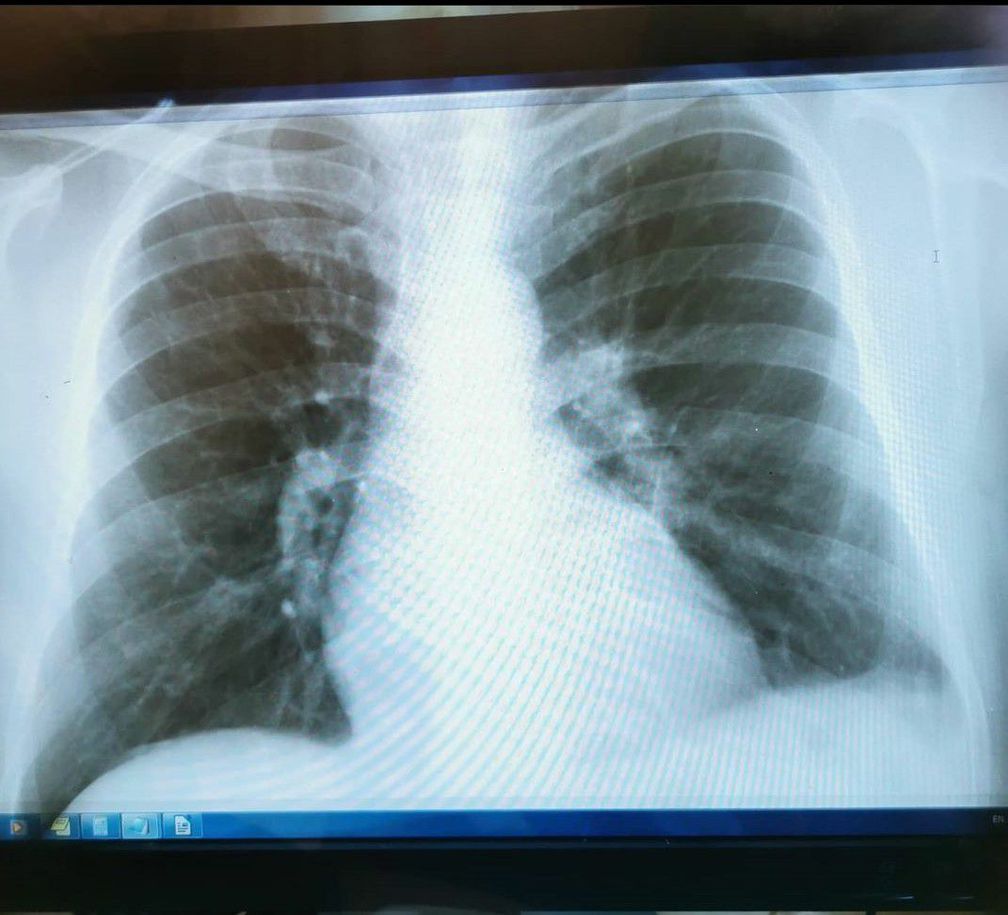

Whats your diagnose ??

Patients come with cough, shortness of breath He reported fever but at clinic his temprature was 36.5 °C Normal no elevation of WBC Age - 40 year

Left plural effusion and calcification of hilar lymph nodes.

İt’s sarcoidoses

And also left pleural effusion because CP angle is widened or not sharp

Tb